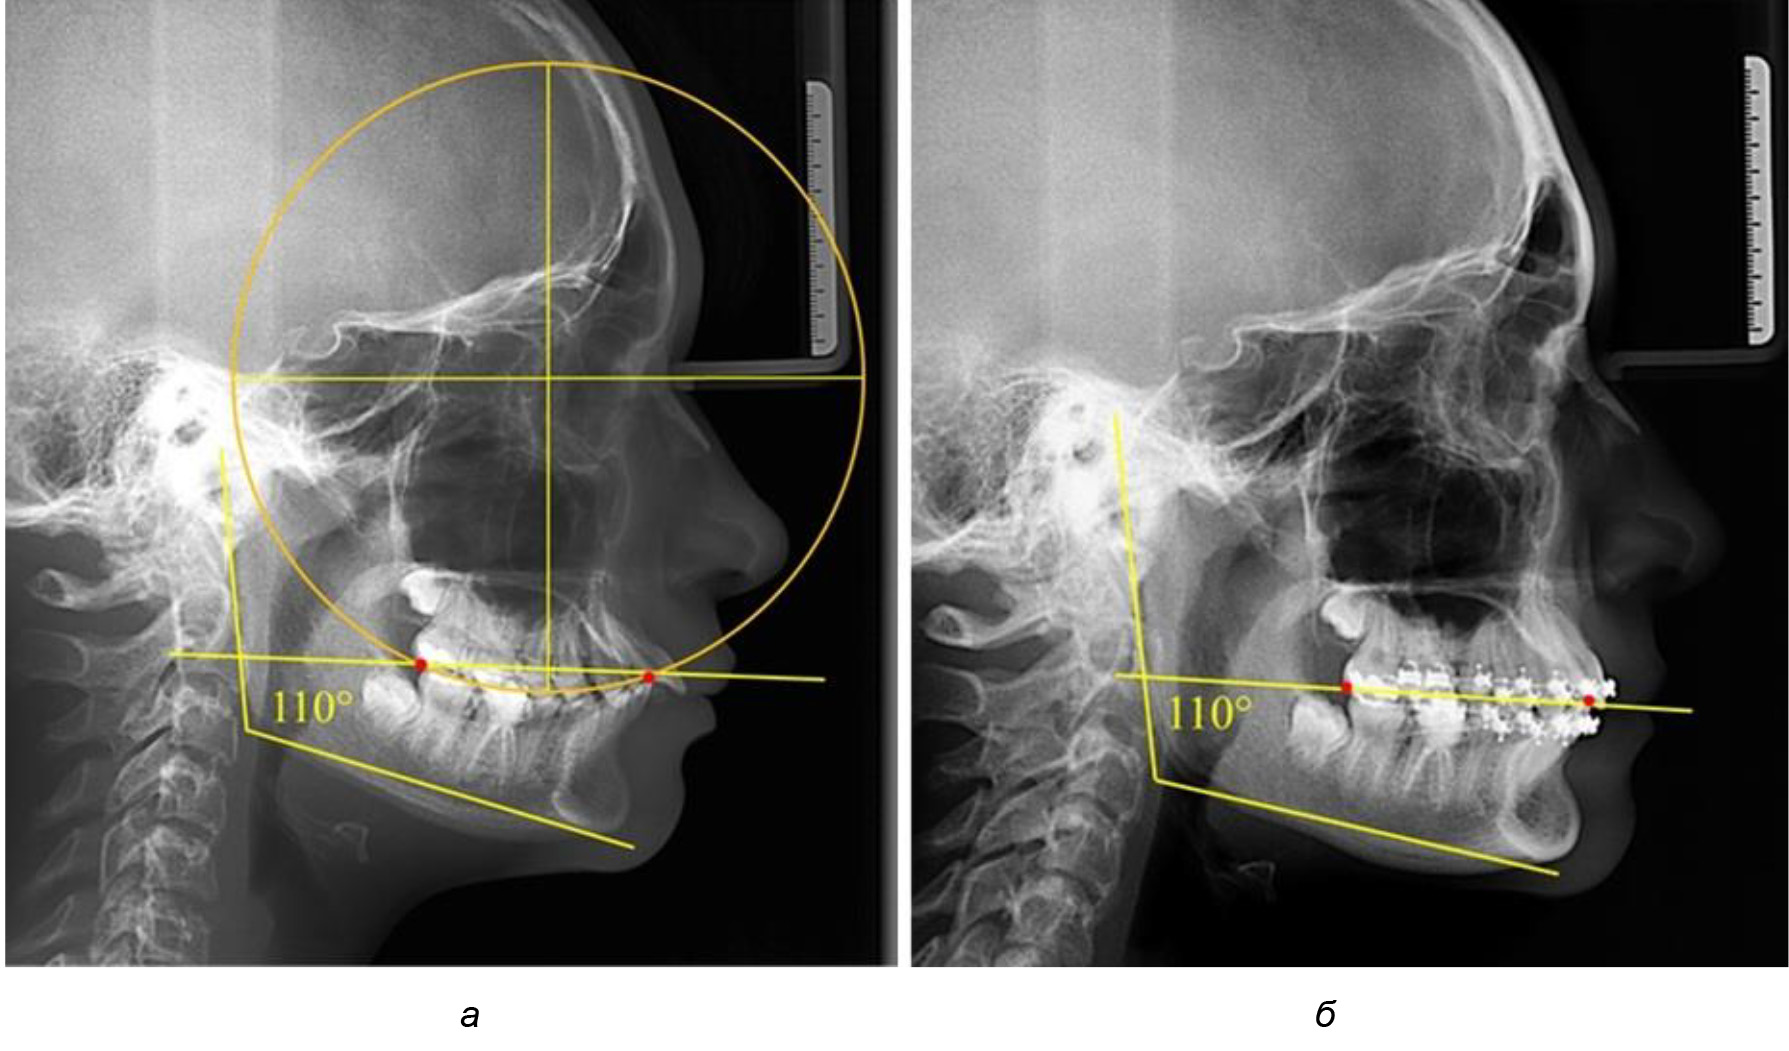

При анализе латеральных ТРГ устанавливали реперный окклюзионные точки в переднем и боковом отделе. Передняя точка устанавливалась на режущем крае нижнего медиального резца, которую в клинике ортодонтии обозначают как vPOcP. Дистальная точка второго нижнего моляра обозначалась как hPOcP. Измеряли расстояние между окклюзионными точками, что определяло сагиттальный размер окклюзионной линии. Использование программ PowerPoint позволило проводить окружность, проходящую по линии смыкания зубов через окклюзионные точки. Измеряли радиус окружности. Учитывая вариабельность размеров окклюзионной линии и радиуса окружности, определяли относительный показатель через отношение радиуса круга к длине сагиттального размера окклюзионной линии. Глубину окклюзионной кривой измеряли от точки наибольшей выпуклости до окклюзионной линии (рис. 1). На ортопантомограмме (ОПТГ) также соединяли окклюзионные точки правой и левой стороны и измеряли глубину окклюзионной кривой от точки наибольшей выпуклости до окклюзионной прямой линии. Результаты глубины кривой Spee сравнивали по данным ТРГ и ОПТГ.

Рис. 1. Метод определения кривой Spee на ТРГ (а) и на ОПТГ (б)

Рис. 5. Особенности ТРГ при патологической кривой Spee до лечения (а) и после лечения (б) техникой «прямой» дуги